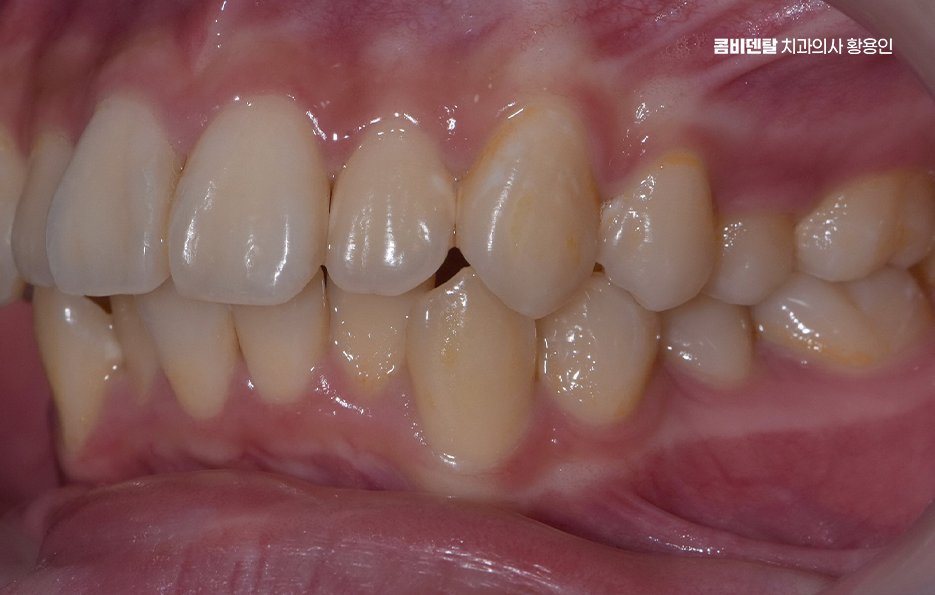

특히 교합이 틀어진 상태에서는 특정 치아에만 씹는 힘이 과도하게 실리게 되는데 이로 인해 일부 치아는 빠르게 마모되거나 깨지게 되고, 반대로 거의 사용되지 않는 치아는 치주 조직이 약해져서 잇몸 퇴축이나 치주염이 생길 확률도 높아지는 거예요. 그리고 치열이 고르지 않은 상태에서는 양치질을 꼼꼼히 해도 치간이나 치아 뒷면에 음식물과 세균이 남기 쉬워서 충치 발생률도 높아지는 건 당연한 것이며 결국 부정교합은 기능적인 저작 문제, 치아의 수명 단축, 잇몸 질환이라는 복합적인 문제로 이어지게 될 수 있어요

부정교합 교정 안하면 또 부정교합이 얼굴형이나 턱관절에 끼치는 영향도 결코 가볍게 봐선 안 되는 부분인데 치아가 가지런하지 않으면 턱의 움직임도 비대칭적으로 진행되기 쉽고 이로 인해 한쪽 턱이 과도하게 발달하거나, 얼굴 한쪽이 더 튀어나와 보이거나, 심한 경우 턱관절에서 ‘딱딱’ 소리가 나거나 입이 잘 벌어지지 않는 턱관절 장애로 발전하는 경우도 있어요

그렇다면 이런 부정교합 문제를 해결하기 위해선 어떤 방식으로 치료계획을 세워야 하느냐가 중요한데 첫 번째 단계는 정밀한 진단과 분석으로 단순히 눈으로 보기엔 어느정도 가지런해 보여도 실제로는 턱의 중심선이 틀어져 있거나, 치아의 경사가 비정상적으로 되어 있을 수 있기 때문에 파노라마 X-ray, 세팔로, 구강 스캐너, 3D CT 등을 통해 턱의 구조, 치아 배열, 뼈 상태 등을 면밀히 분석해야 정확한 치료계획이 세워지는 거예요.